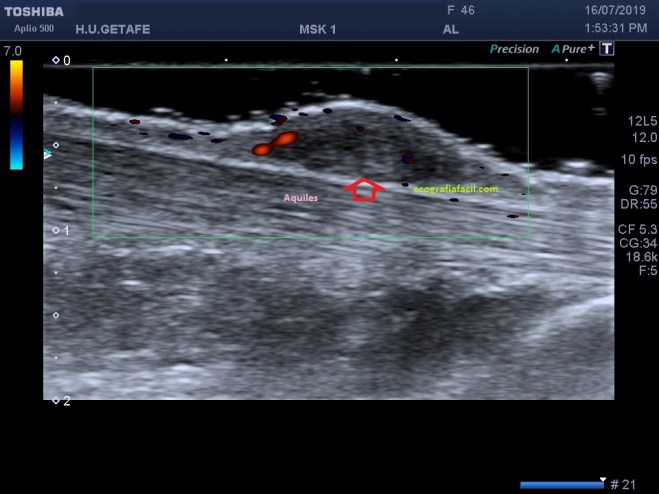

En la imagen 2 puedes ver como la lesión no corresponde ni está en contacto con el aquiles, pertenece claramente al tejido celular subcutáneo.